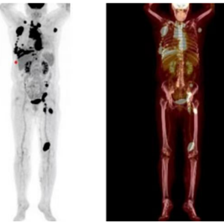

65岁女性患者,2024年8月出现下腹部不适,后出现右上腹痛并加重,近1月体重下降8斤。2024年12月就诊完善检查:乙型肝炎病毒表面抗原阳性(乙肝病毒DNA <500 IU/ml),β2-微球蛋白4.27 mg/L↑,乳酸脱氢酶1011.90 U/L↑。超声提示双侧颈部、右腋下(最大5.7*4.8cm)、左腹股沟多发肿大淋巴结。右腋窝淋巴结穿刺病理诊断为弥漫性大B细胞淋巴瘤,免疫组化示:CD20(+)、CD10(-)、BCL6(+,约35%,热点区约60%)、MUM1(+)、BCL-2(+,约80%)、C-Myc(+,约40%)、P53(+,约10%)、Ki-67(+,约80%),符合non-GCB型(Hans分型)及双表达表型;EBER(-)。骨髓未见侵犯。PET-CT提示多发高代谢病灶,累及双锁骨上、纵隔、右腋窝、右胸壁、右眶内、右侧胸膜、心包、左腹股沟、左腘窝等多部位,伴心包及右侧胸腔积液;诊断为:非霍奇金淋巴瘤 弥漫性大B细胞淋巴瘤(non-GCB型,双表达,IV期A组,IPI评分4分高危),慢性HBV感染。

2024-12 PET-CT检查提示膈肌上下多发高代谢淋巴结